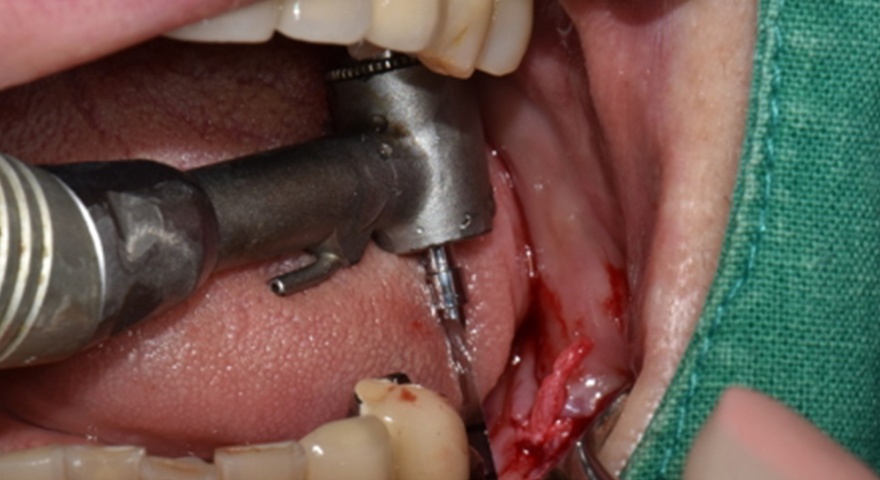

Після проведення стандартної імплантації в ділянках з оголеною різьбою було застосовано техніку DUK: на імплантат наносили спочатку пастоподібний матеріал, далі — гранули, після чого укладали мембрану та закривали клапті швами без натягу. Всі пацієнти отримували антибіотики (амоксицилін) та знеболення (ібупрофен), а через шість місяців — проходили контроль та біопсію ділянки.

Етапи встановлення імплантату та необхідні інструменти:

1) Свердло списоподібне для короткого імплантату INNO

2) Свердло коротке зі стопером 7 мм

3) Свердло діаметром 2,0 зі стопером 7 мм

4) Свердло діаметром 3,5 зі стопером 7 мм

5) Свердло діаметром 5,0 зі стопером 7 мм

6) Короткий імплантат діаметром 5,0

7) Імплантовод ручний

8) Сила використання динамометричного ключа 40 Н/см